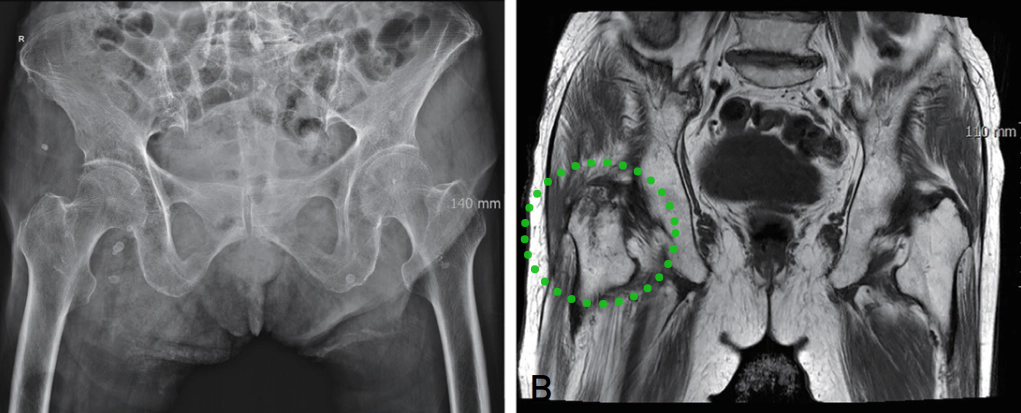

▲ 图示87岁女性患者,摔伤致右髋部疼痛。A:X线检查提示右髋孤立性大转子骨折;B:骨扫描提示孤立性大转子骨折;C:MR提示右股骨粗隆间骨折。

39例同时行磁共振和骨扫描的患者中,35例(89.7%)两检查结果一致,4例结果不一致的患者中,骨扫描提示为孤立性大转子骨折,而磁共振显示为隐匿性转子间骨折。